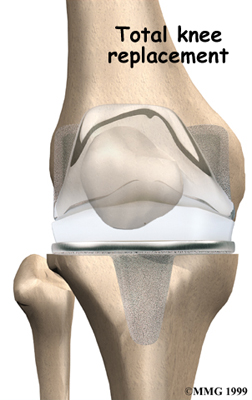

Artificial Knee Replacement

An artificial knee replacement is the ultimate solution for advanced knee OA.

Surgeons prefer not to put a new knee joint in patients younger than 60. This is because younger patients are generally more active and might put too much stress on the joint, causing it to loosen or even crack. A revision surgery to replace a damaged prosthesis is harder to do, has more possible complications, and is usually less successful than a first-time joint replacement surgery.

Related Document: FYZICAL Gainesville's Guide to Artificial Joint Replacement of the Knee